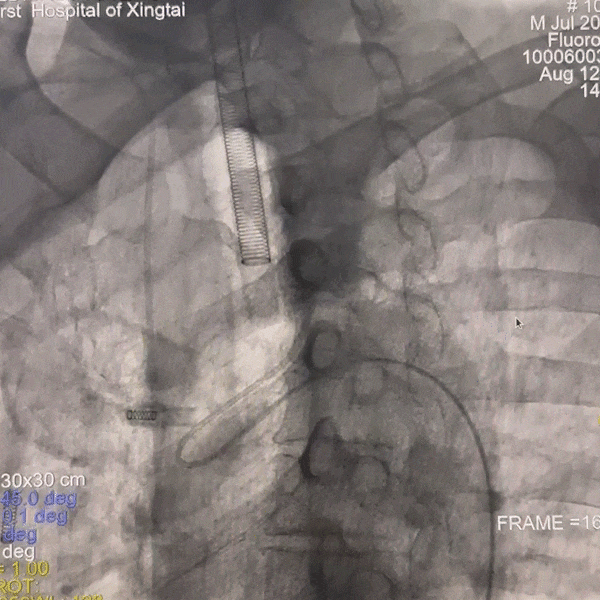

撤出多功能导管和短鞘,交换088输送导管至右侧锁骨下动脉近端,沿输送导管送入赛诺神畅APEX TRA GC™5F-130cm SIM2至主动脉弓,成袢后轻松超选入右侧颈总动脉,同轴沿SIM2导管将输送导管送入右侧颈总动脉,撤出SIM2导管,沿导丝将6F 115cm远端通路导管送至右侧颈内动脉C4段。

动脉长鞘怎么置入一技之“长”丨经桡及经股困难入路应用赛诺神畅APEX TRA GC™导引导管建立通路病例合集_https://www.jmylbn.com_新闻资讯_第33张

路图下上导丝、导管

动脉长鞘怎么置入一技之“长”丨经桡及经股困难入路应用赛诺神畅APEX TRA GC™导引导管建立通路病例合集_https://www.jmylbn.com_新闻资讯_第34张

SIM2导引导管超选右侧颈总动脉

动脉长鞘怎么置入一技之“长”丨经桡及经股困难入路应用赛诺神畅APEX TRA GC™导引导管建立通路病例合集_https://www.jmylbn.com_新闻资讯_第35张

跟进输送导管

动脉长鞘怎么置入一技之“长”丨经桡及经股困难入路应用赛诺神畅APEX TRA GC™导引导管建立通路病例合集_https://www.jmylbn.com_新闻资讯_第36张

交换远端通路导管

撤出微导丝,沿球囊扩张导管送入4.5*14mm 支架,精确定位后缓慢释放支架。

动脉长鞘怎么置入一技之“长”丨经桡及经股困难入路应用赛诺神畅APEX TRA GC™导引导管建立通路病例合集_https://www.jmylbn.com_新闻资讯_第44张

释放支架